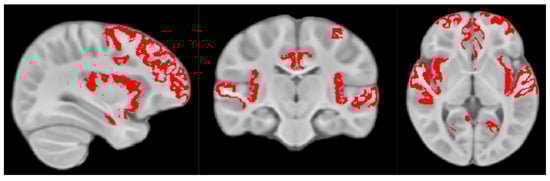

2.2. Myelin Magnetic Resonance Imaging (MRI) Data Acquisition and Processing